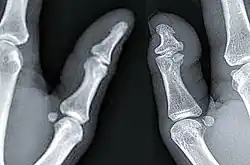

X-ray of a regular thumb (left) and a thumb with brachydactyly type D (right) showing distal phalange brachyphalangy of said thumb.

Brachydactyly type D is a skeletal condition that exhibits a “partial fusion or premature closing of the epiphysis with the distal phalanx of the thumb,” according to Goodman et alia (1965).[6] J.K. Breitenbecher (1923) found that the distal phalanges of short thumbs were one-half the length of full-length thumbs, while R.M. Stecher (1957) claimed that it is approximately two-thirds. The condition may be unilateral (affecting one thumb) or bilateral (affecting both).[6]